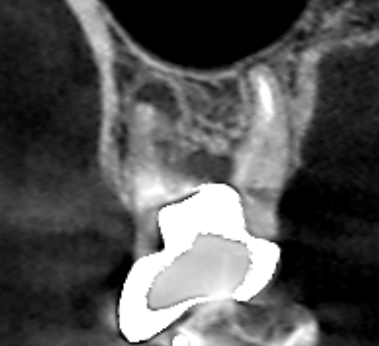

上顎第一大臼歯の初診時の冠状断のCT画像です。

赤い矢印の先の歯根の分岐部に黒い膿の影がみられます。土台が歯根の分岐部を貫通しているのが、膿の原因と考えられます。